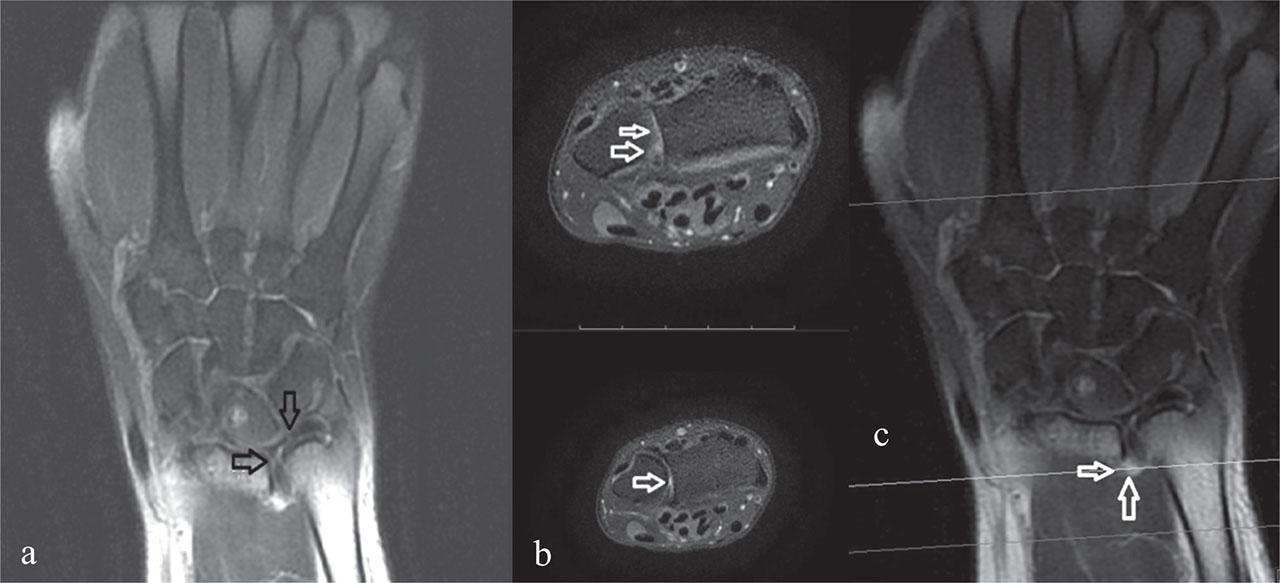

On physical examination at our clinic, the patient had ulnar foveal tenderness and pain with ulnar deviation and forearm rotation. In addition to the positive TFCC compression and supination tests performed earlier, TFCC stress and grind tests were also positive. Other systems were unremarkable. Magnetic resonance imaging (MRI) of the left wrist showed joint effusion in the distal radioulnar joint and the TFCC appeared thickened, with increased signal intensity consistent with the injury (Figure 2). An 8 mm lesion in the lunate bone showed hypointensity on T1-weighted images and hyperintensity on T2-weighted images, consistent with a bone cyst. The bony structures, muscles, and tendons of the wrist demonstrated homogeneous signal intensity. The joint spaces between the carpal bones were of normal width. No pathological findings were observed in the muscles or soft tissues within the imaging field.

T2-weighted MRI of the left wrist showing: a) increased thickness and signal intensity of the triangular fibrocartilage complex (TFCC) (arrows); b) and c) joint effusion in the distal radioulnar joint (arrows) consistent with a TFCC injury